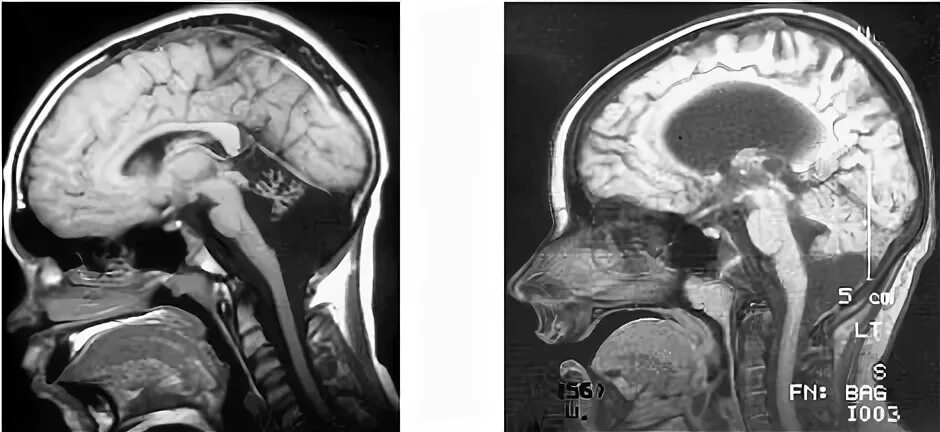

Денди уокера мрт